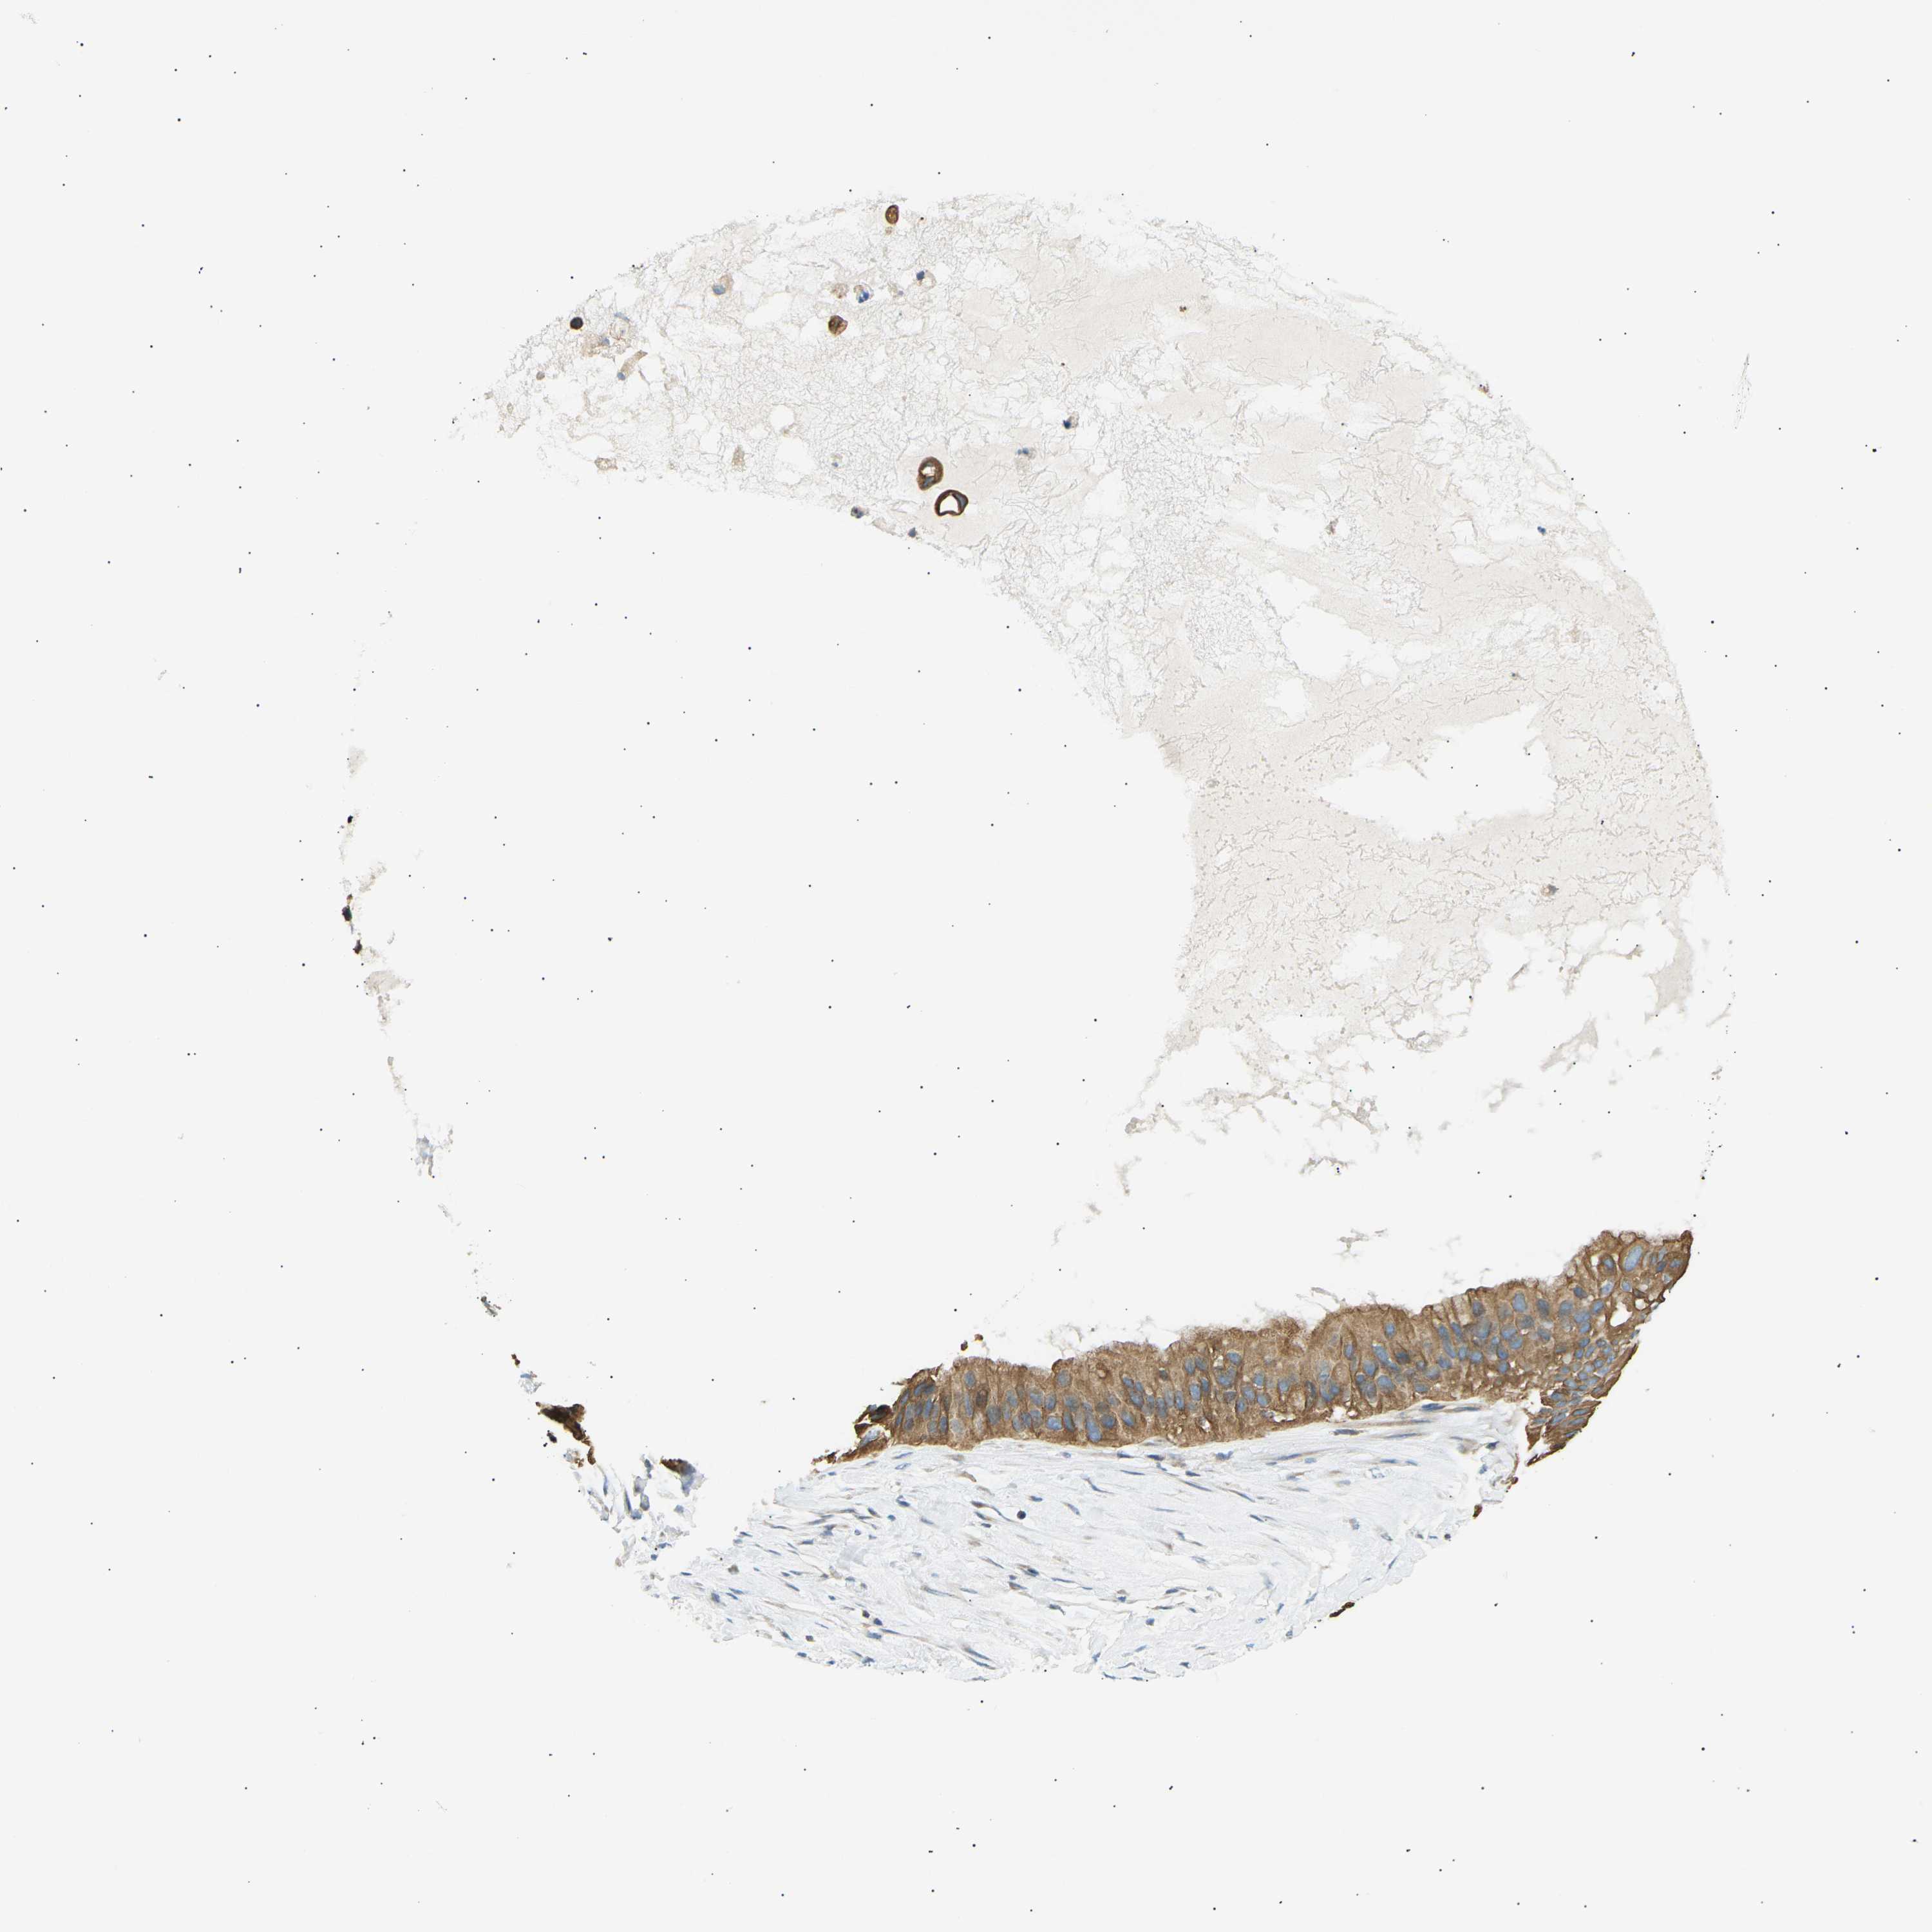

OVARIAN CANCER - Protein expressioni

A mouse-over function shows sample information and annotation data. Click on an image to view it in a full screen mode. Samples can be filtered based on level of antibody staining by selecting one or several of the following categories: high, medium, low and not detected. The assay and annotation is described here.

Note that samples used for immunohistochemistry by the Human Protein Atlas do not correspond to samples in the TCGA dataset.

Antibody stainingi

Antibody staining in the annotated cell types in the current human tissue is reported as not detected, low, medium, or high, based on conventional immunohistochemistry profiling in selected tissues. This score is based on the combination of the staining intensity and fraction of stained cells.

Each image is clickable and will lead to virtual microscopy that enables deeper exploration of all samples and also displays staining intensity scores, fraction scores and subcellular localization as well as patient and tissue information for each sample.

Antibody CAB015211

Cystadenocarcinoma, serous, NOS

Carcinoma, endometroid

Cystadenocarcinoma, mucinous, NOS

Carcinoma, NOS